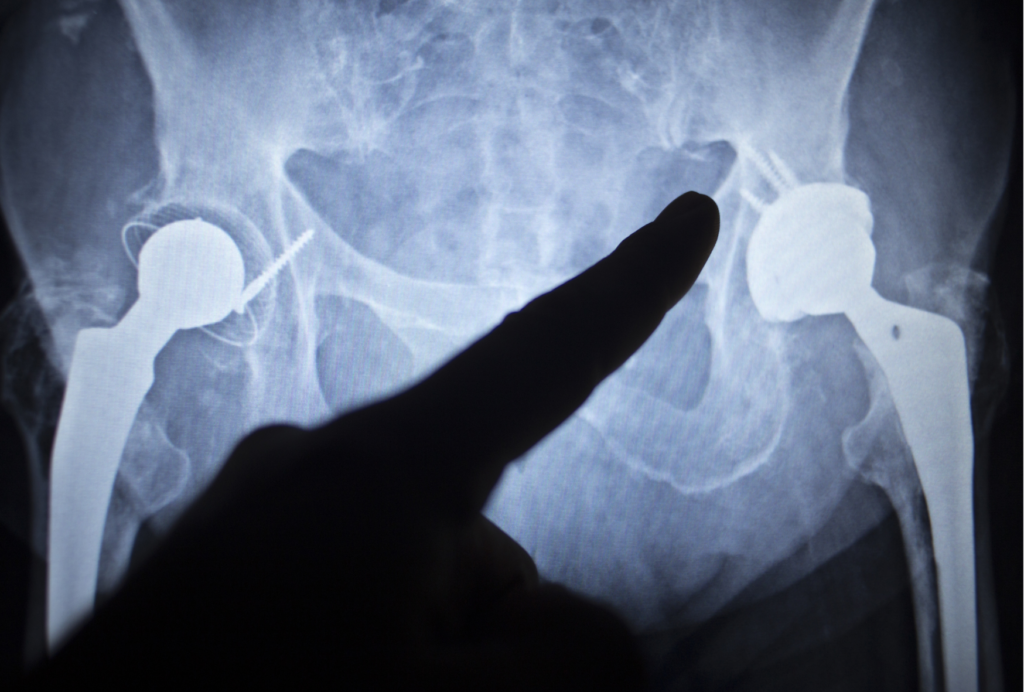

一方で、レントゲンで関節裂隙の消失や強い変形が確認され、痛みや可動域制限が強い場合には、手術を含めた選択肢が検討されるケースもあると言われています。人工股関節置換術などは代表的な方法として紹介されていますが、適応は総合的に判断されるとされています。